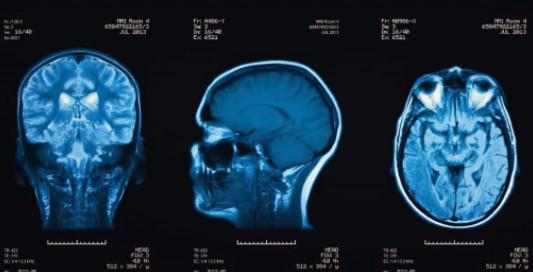

头部外伤脑震荡x线扫描